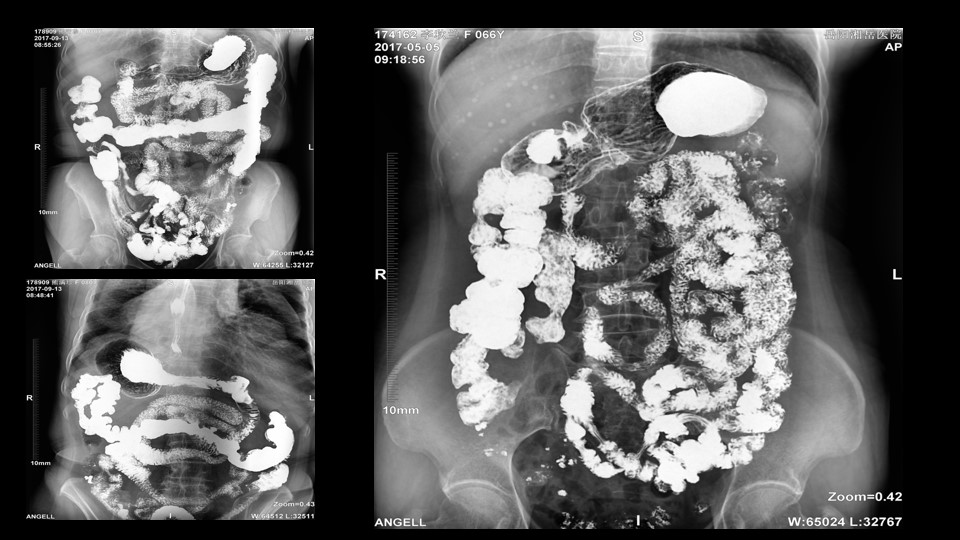

会议开始,岳阳市医学会放射分会副主委、湘岳医院放射科蔡雨主任,结合自身在放射影像的20多年经验,为参会嘉宾分享了动态DR在消化道造影中的应用价值。作为动态DR用户,蔡雨主任结合动态DR的实际拍片与操控经验,分享了动态DR技术在相关群体疾病检查上的独到优势和人文关怀。蔡雨主任说到:“随着内镜技术的发展以及CT、MR的发展,消化道造影在减少,但是这并不意味着消化道造影的价值在下降。以老年人为例,很多老年群体都患有严重的心肺疾病、或者消化道畸形,很多老年人本身就有糖尿病、高血压等等综合疾病,传统内镜的检查对于这类群体来说是一件难以忍受的痛苦,而动态DR的多项创新技术让这类群体的消化系统疾病筛查变得更为人性和精准。任何一个好的消化道造影,一定是患者、诊断医生、临床医生三方满意的结果。德赢VWIN科技动态DR技术利用900万像素高清拍片、大幅面透视、高清点片、视频保存与回放等核心功能,完全满足临床对消化道气钡双重造影检查的需要。图像质量全面超越以往模拟胃肠机、影增数字胃肠机”。蔡雨主任全面演示了动态DR在食道造影、上消化道造影、小肠双对比造影、结肠气钡双对比造影中的应用,通过动态DR可以清晰获得临床诊断和评估的图像依据。

▲蔡雨主任使用动态造影图像示例